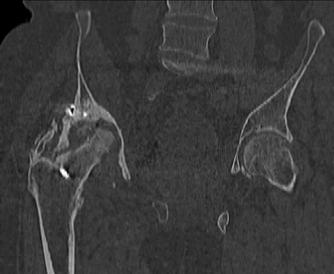

Пациент 49 лет, паровозная травма 23.2.2006, получил вертикальная нестабильное повреждение таза, разрыв левого крестцово-подвздошного сочленения, перелом лонной, седалищной костей слева, T-образный оскольчатый перелом правой вертлужной впадины с переломом заднего края, вывих правого бедра, посттравматическая пояснично-крестцовая плексопатия с обеих сторон, паралич мышц правой голени. В день травмы - вправление вывиха, скелетное вытяжение, 14.3.2006 чрескостный остеосинтез таза. 20.4.2006 остеосинтез правой вертлужной впадины пластинами, осложнившийся нагноением межмышечной гематомы правой ягодичной области. Получал консервативное лечение, было достигнуто полное заживление раны. 24.7.2006 введены илиосакральные винты слева. С декабря 2006 года и по настоящее время ходит на костылях без опоры на правую ногу. Планируется THA. Помогите определиться с вариантом костной пластики? И какую укрепляющую конструкцию использовать?